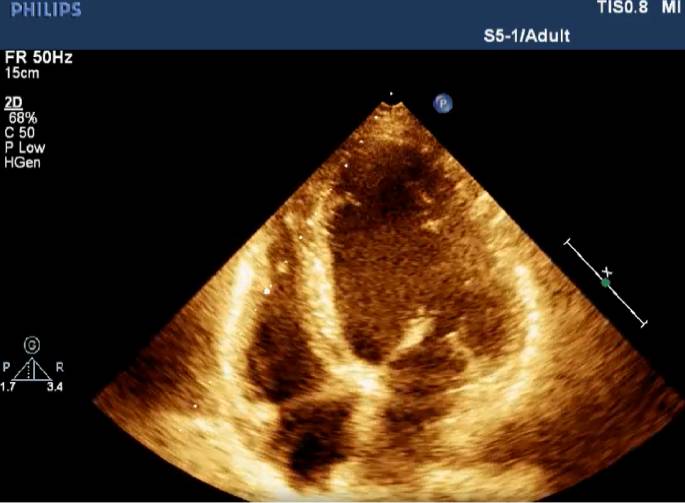

Echocardiography

• Basic Echo Course online

• Offered by Dr. K K Kapoor - renowned non-invasive cardiologist at Appolo Hospitals New Delhi

• Suitable For Emergency doctors , Cardiologists, Anesthesiologists, Physicians

• Course duration 4 Weeks

• Course fee INR 40K (Including Taxes)